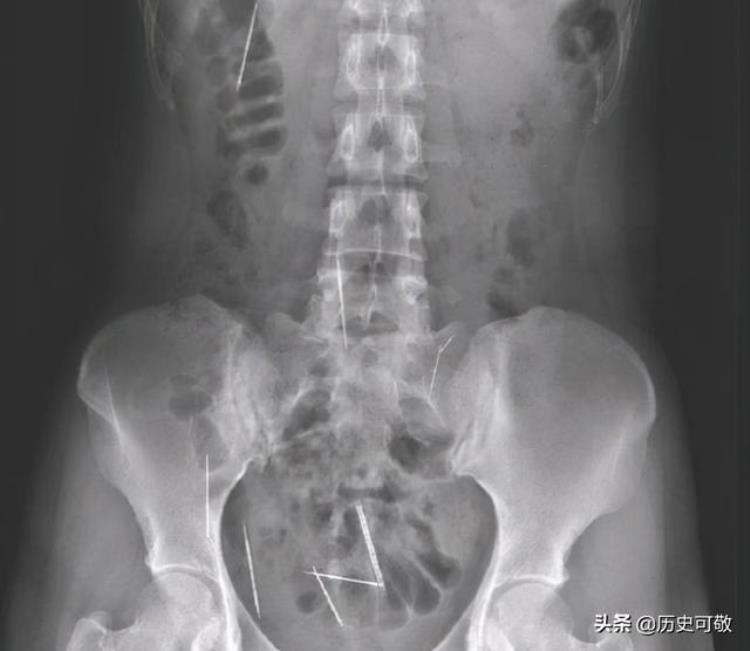

医生把罗翠芬的X光片递给她看,在 X光片上,罗翠芬清晰地看到在她的头部,颈部,腹部,胸部,腿部,全身从上到下都遍布显著的针状物,罗翠芬赶紧数了一下,一共有26根。

8月30日徐梅召集医院专家进行了联合的会诊,发现罗翠芬体内26根缝衣针错综复杂,腹部的6根还处于游走的状态,随时有可能刺破血管引发生命危险,如果不尽快手术,罗翠芬十分危险,因此徐梅决定放手一搏,尽快给罗翠芬安排手术。